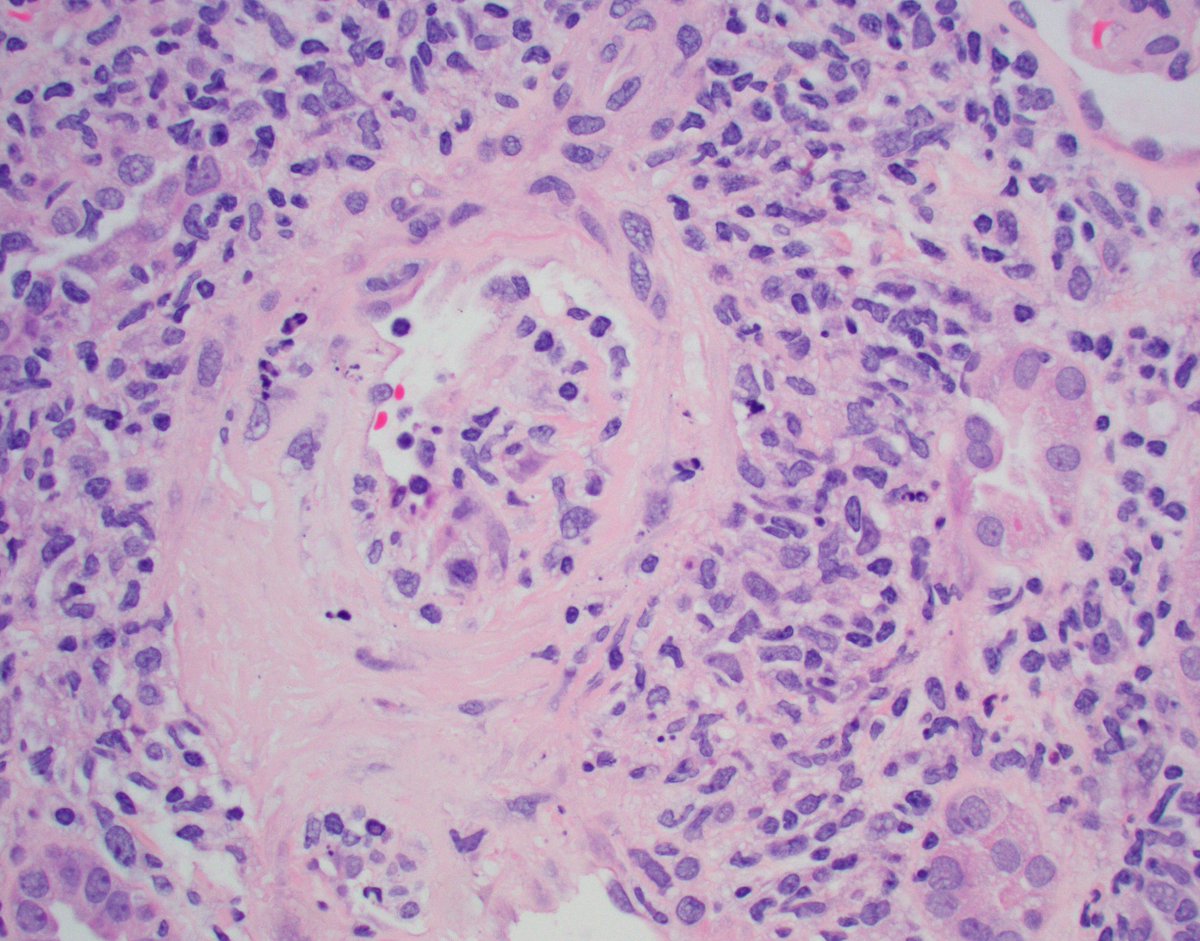

Mini case-series of crystal-storing histiocytosis (CSH) affecting predominantly glomerular loops with detailed literature review of renal CSH, images of one of the cases are depicted below, authors.elsevier.com/c/1Zh4S3uV~y8B…